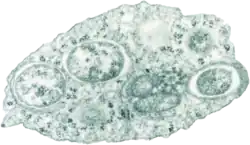

Micrografía de microscopio electrónico mostrando el virus causante de la fiebre hemorrágica del dengue | ||

El dengue es producido por un virus del grupo de los arbovirus (llamados así porque son transmitidos a través de artrópodos hematófagos), familia de los Flaviviridae, género Flavivirus. La partícula viral tiene forma esférica y mide entre 30 y 50 nm. Posee una envoltura proteica (principalmente E y M) que la cubre por completo. El material genético se encuentra contenido en un nucleocápside circular, y entre este y la cubierta se encuentra una bicapa lipídica que es formada a partir de lípidos extraídos de la membrana celular de la célula huésped. El genoma se compone de una sola cadena de ARN de tipo lineal, sentido positivo y gran variabilidad. El virus es altamente inestable en el medio ambiente, inactivándose con el calor, desecación y desinfectantes que contengan detergentes o solventes lipídicos.

El virus del dengue, al igual que otros flavivirus, contiene un genoma de ARN rodeado por una nucleocápside de simetría icosaédrica, de 30 nm de diámetro, la cual está constituida por la proteína C ―de 11 kd― y una envoltura lipídica de 10 nm de grosor asociadas a una proteína de membrana (M) y otra de envoltura (E), que da lugar a las proyecciones que sobresalen de la superficie de los viriones.[31]